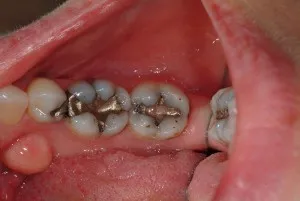

20 year old amalgam (silver/mercury) restorations that appear in tact and are not causing pain or discomfort.